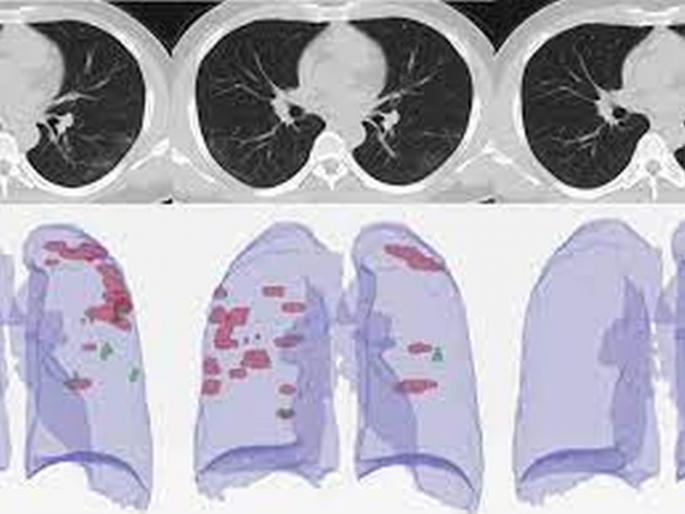

CT Scan scores : सीटीस्कॅनचा स्कोअर चिंताजनक असल्याचे काही रुग्णांमध्ये पाहावयास मिळत आहे.

अकोला : मागील काही दिवसांपासून कोरोना रुग्णसंख्या वाढ आणि त्यातून होणारे मृत्यू याचे प्रमाण लक्षणीय वाढले आहे. यामध्ये बहुतांश रुग्ण गंभीर अवस्थेत आहेत, मात्र याशिवाय आरटीपीसीआर निगेटिव्ह असलेल्या रुग्णांमध्येही कोरोनाची गंभीर लक्षणे आढळून येत असून त्यांचा सीटीस्कॅनचा स्कोअर चिंताजनक असल्याचे काही रुग्णांमध्ये पाहावयास मिळत आहे. या रुग्णांची स्थितीही गंभीर असून, त्यांच्यावरही कोविड उपचार आवश्यक असल्याचे काही डॉक्टरांचे मत आहे. नव्या वर्षात फेब्रुवारीपासूनच कोरोनाने कहर करण्यास सुरुवात केली आहे. मार्चनंतर आता एप्रिलमध्येही कोविडच्या गंभीर रुग्णांसोबतच मृत्यूची संख्याही झपाट्याने वाढत आहे. कोरोनाच्या गंभीर रुग्णांसोबतच आरटीपीसीआरचा अहवाल निगेटिव्ह असलेल्या रुग्णांमध्ये कोरोनाची गंभीर लक्षणे दिसून येत आहेत. सीटी स्कॅनच्या अहवालात रुग्णांना संक्रमण झाल्याचे अनेक रुग्णांमध्ये दिसून येत आहे. अशा रुग्णांवर कोविड ऐवजी न्युमोनियाचा रुग्ण म्हणून काही ठिकाणी उपचार केला जात आहे. या रुग्णांना योग्य वेळी योग्य उपचार न झाल्यास त्यांच्या जीवाला धोका उद्भवू शकतो. शिवाय, अशा रुग्णांना सामान्य वॉर्डात उपचारासाठी ठेवल्यास त्यांच्यापासून इतर नॉनकोविड रुग्णांनाही कोरोनाचा संसर्ग होण्याची शक्यता नाकारता येत नाही. रॅपिड किंवा आरटीपीसीआर अहवालालाच मान्यता सद्यस्थितीत रॅपिड तसेच आरटीपीसीआर चाचणीसोबतच सीटी स्कॅनद्वारे कोविडची चाचणी करण्याचे प्रमाण वाढले आहे, मात्र रॅपिड आणि आरटीपीसीआर वगळल्यास इतर कुठल्याच चाचणीला मान्यता नाही. त्यामुळे सीटी स्कॅनच्या अहवालानुसार रुग्णाची स्थिती चिंताजनक असली, तरी त्याला कोविड रुग्ण म्हणून रुग्णालयात दाखल करण्यात येत नसल्याची माहिती वैद्यकीय अधिकाऱ्यांनी दिली. स्वतंत्र वॉर्डात उपचाराची गरज आरटीपीसीआर अहवाल निगेटिव्ह असला, तरी सीटी स्कोअर आणि रुग्णाला असलेल्या कोविडच्या लक्षणांमुळे रुग्णांची स्थिती चिंताजनक आहे. या रुग्णांकडून इतरांनाही संसर्ग होण्याची शक्यता वाढते. त्यामुळे अशा रुग्णांवर कोविड वॉर्डात किंवा स्वतंत्र वॉर्डात उपचार करण्याची गरज असल्याची माहिती डॉक्टरांनी दिली. ही आहेत रुग्णांमध्ये लक्षणे श्वास घेण्यास त्रास सुगंध किंवा दुर्गंध न येणे जिभेला चव नसणे ताप येणे सर्दी, खोकला